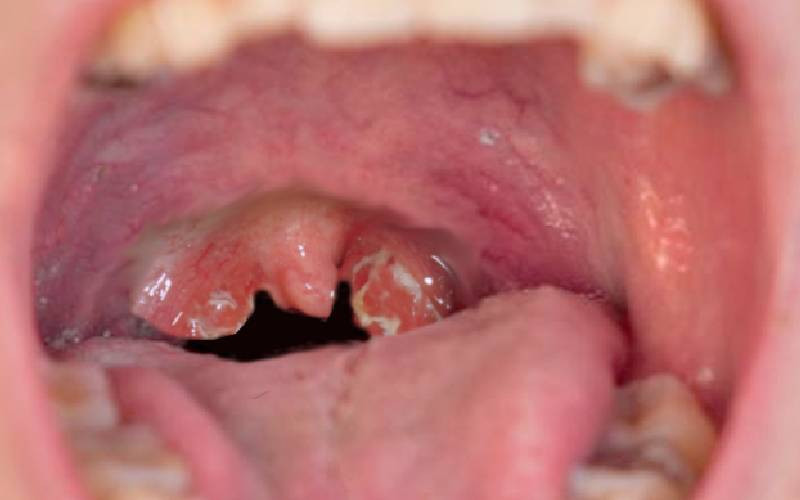

Adenoids: Hidden culprit behind recurrent coughs, loud snoring